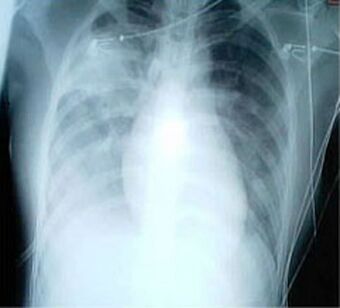

| A chest X-ray showing increased opacity in both lungs, indicative of pneumonia, in a patient with SARS |

For a case to be considered probable, a chest X-ray must be positive for atypical pneumonia or respiratory distress syndrome.

The appearance of SARS in chest X-rays is not always uniform but generally appears as an abnormality with patchy infiltrates.[7]